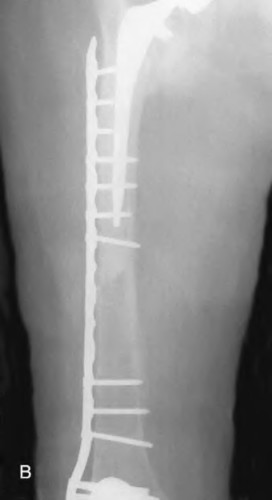

A 72-year-old male presents 2 years status post fixation of an impending pathologic right femur fracture due to metastatic renal cell carcinoma. He is minimally ambulatory due to pain. Despite radiation therapy, there has been progression of the lesion with extensive cortical bone loss, which is shown in Figure A. A proximal femoral replacement arthroplasty is performed without complications, and is demonstrated in Figure B. Which of the following is true regarding this patients post-operative course?

Deep prosthetic infection is the most common complication after hip arthroplasty performed for salvage of failed internal fixation after pathologic proximal femoral fracture secondary to malignancy.

Jacofsky et al reviewed the complications in 42 patients with a mean age of 63 who were treated with hip arthroplasty for salvage of failed treatment of a pathologic proximal femoral fracture. Multiple different constructs were used.

The most common complication was deep prosthetic infection, which occurred in nearly 10% of the patients studied. All infections occured in patients whom had previously received radiation. The mean Harris Hip score improved from 42 to 83 points post-operatively, and 41 of the 42 patients were ambulatory at follow-up. Implant survivorship free of revision for any reason at 5 years was 90%, and free of revision for aseptic failure or radiographic failure was 97%.

Figure A shows a lytic lesion of the proximal femur with an intramedullary implant. Figure B shows a proximal femoral replacement.